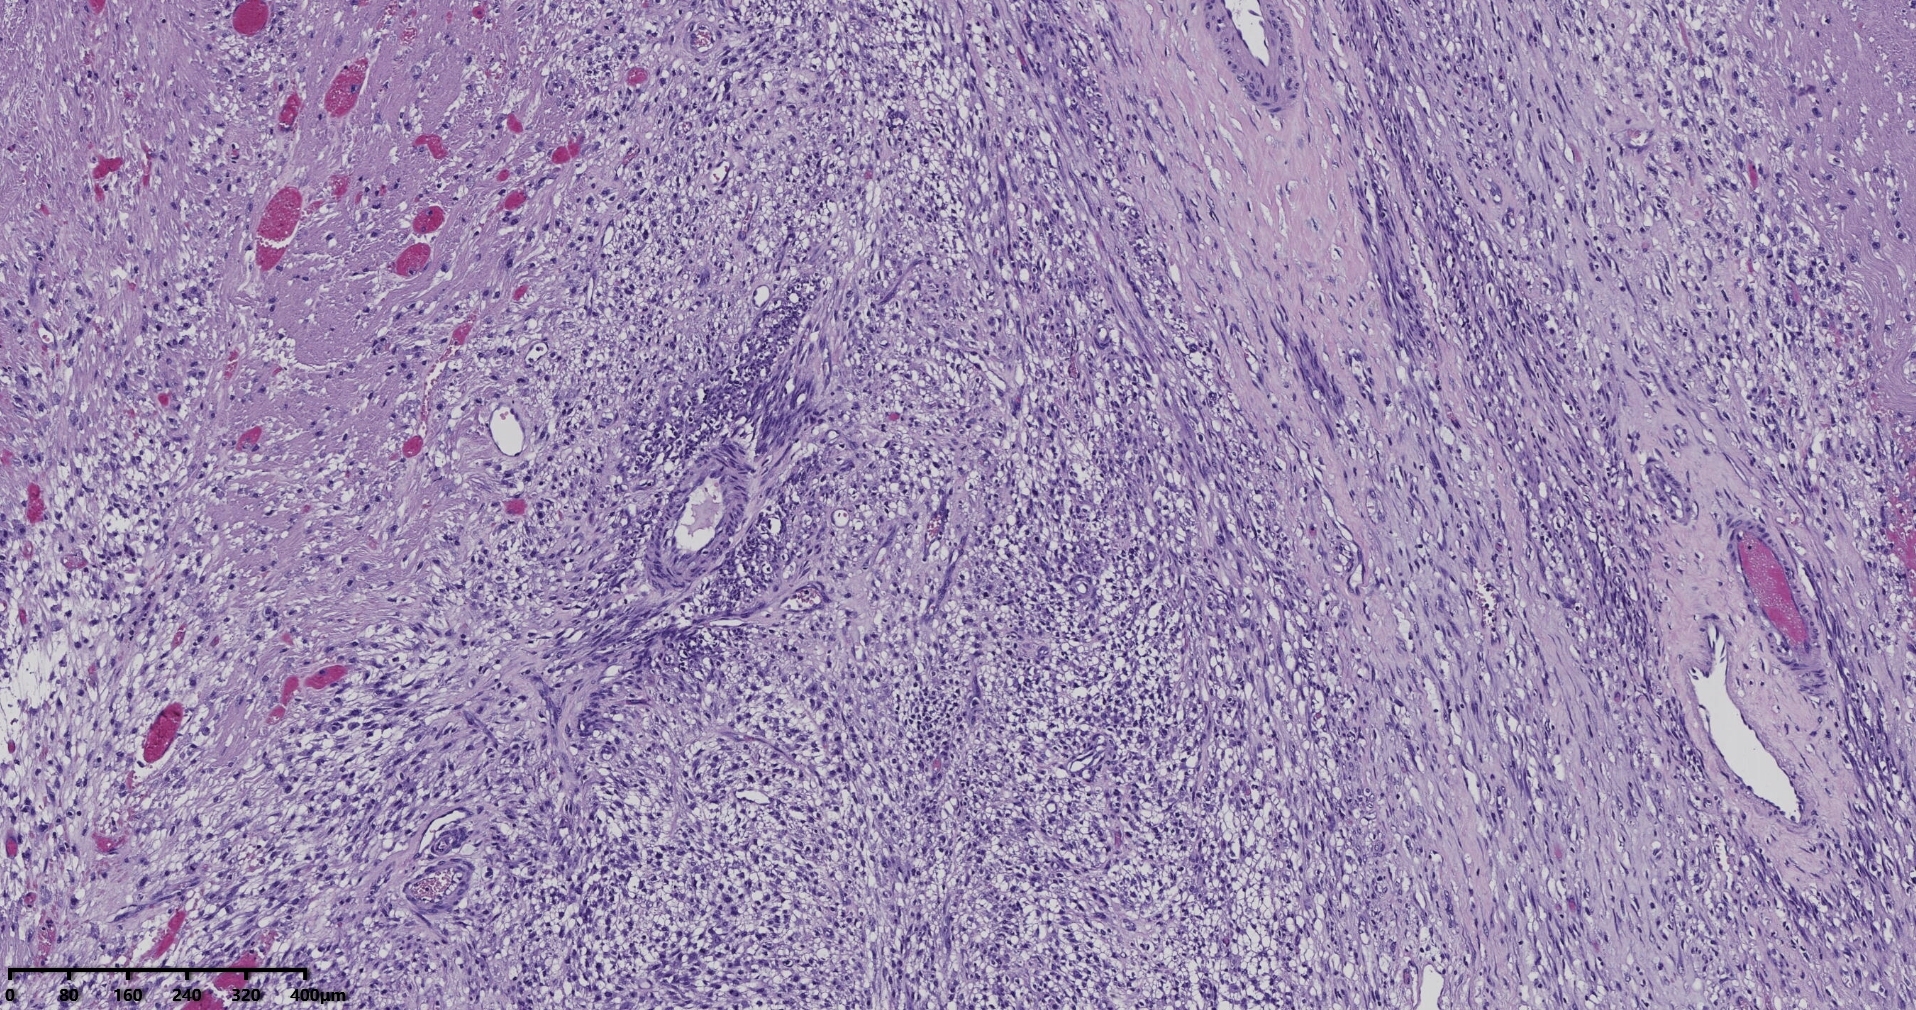

镜下所见小肿物无特殊,大肿物瘤细胞密集,中心区有变性、坏死,瘤细胞核有异型性。大肿物补充取材,发现,部分区域切面灰黄,这个区域,瘤细胞更密集,异型性更显著。肿物边缘有薄层正常平滑肌组织被覆,靠近边缘瘤细胞最密集,局部瘤组织内小血管较丰富。

会诊:考虑平滑肌肉瘤。

北医三院会诊:子宫平滑肌瘤伴红色变性可能性大,建议加做免疫组化及NGS检测进一步明确诊断。